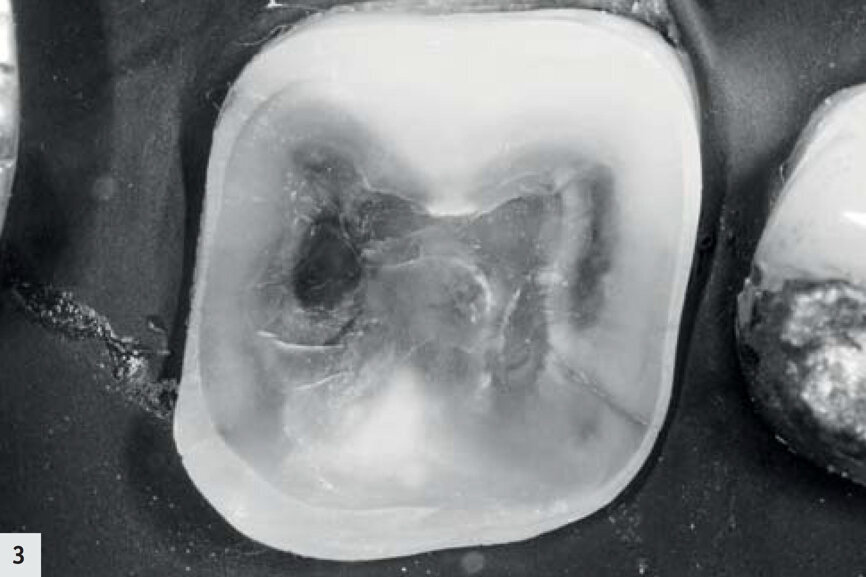

Fig. 2 : Après l’élimination de l’amalgame, on pouvait observer une fissure dans la partie mésio-linguale de la dent. Cette dent est fortement colorée par des produits résultant de la corrosion.

Fig. 3 : Même dent, nettoyée par air-abrasion.

Les deux cas présentés par la suite illustrent comment le mode détection se révèle utile dans le cadre de votre pratique quotidienne. Un patient s’est présenté avec une ancienne restauration à l’amalgame défectueuse (Fig. 1). Après l’élimination de l’amalgame, des produits résultant de la corrosion et une fissure présente jusque dans la dentine ont été détectés dans la zone mésio-linguale ; l’aspect de la dentine environnante était légèrement plus sombre (Figs. 2–3). Sous le rayonnement proche-UV du mode détection, elle est apparue sous la forme d’une très fine ligne violette, due à la diffraction de la lumière au niveau de la fissure ; toutefois, la dentine environnante s’est révélée saine et sans métabolites bactériens, dans la mesure où aucune fluorescence rouge-orangée n’était observée (Figs. 4–5). Les cuspides ont été réduites afin de minimiser le risque d’une propagation de la fissure, mais aucune préparation supplémentaire n’a été nécessaire.